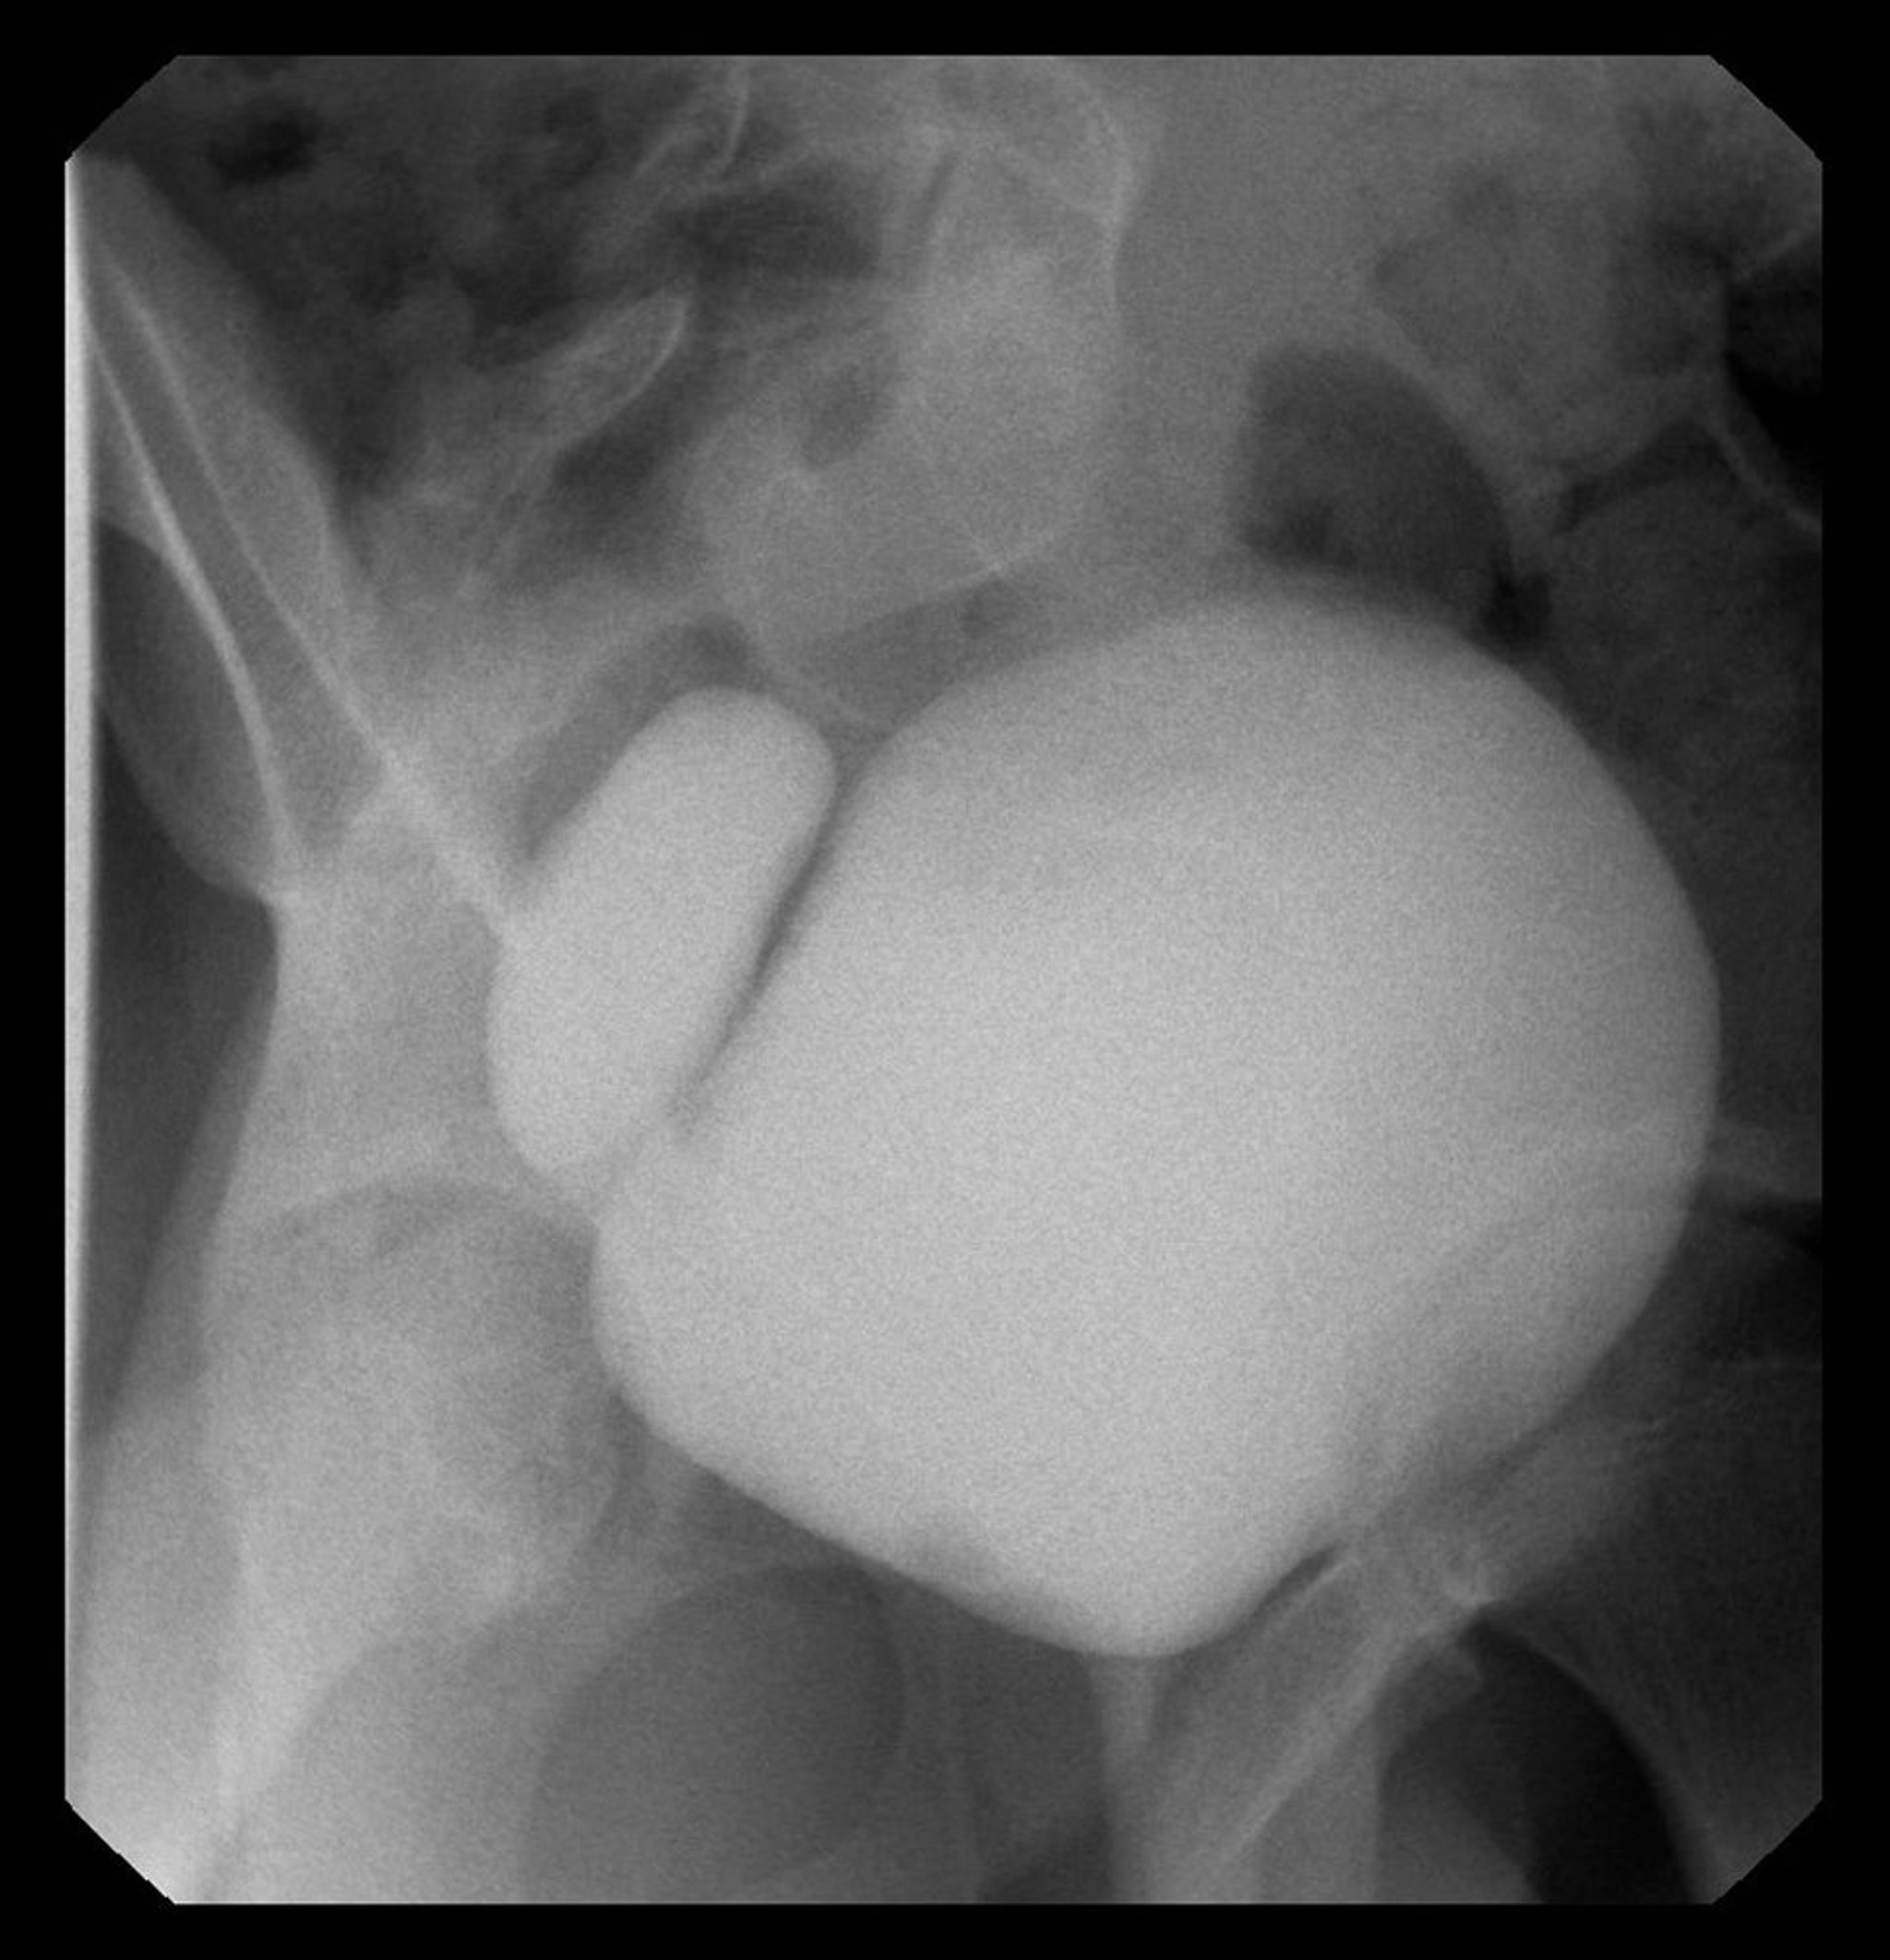

Cette image montre un cystogramme avec diverticule de la vessie à droite.

Image courtoisie de Drs. Ronald Rabinowitz et Jimena Cubillos.